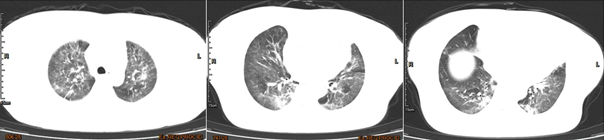

患者,女性,74岁,主诉“胸闷、气促3月,加重伴发热5天”。类风湿关节炎病史10余年,近3月余因多处关节反复疼痛,持续口服甲泼尼龙片。睡眠障碍伴抑郁症病史约10年,冠心病病史近10年。先后2次行PCI术,置入2枚冠脉支架。3个月前曾出现血糖升高。查体:体温37.2℃,BP 143/64 mmHg,R 18~24次/min,SpO74%(不吸氧状态)。双肺弥漫性渗出改变,考虑PJP、CMV感染可能性大。

图片

外周血mNGS回报耶氏肺孢子菌(序列数32)、CMV(序列数2499)。ptNGS同样检出耶氏肺孢子菌和CMV。